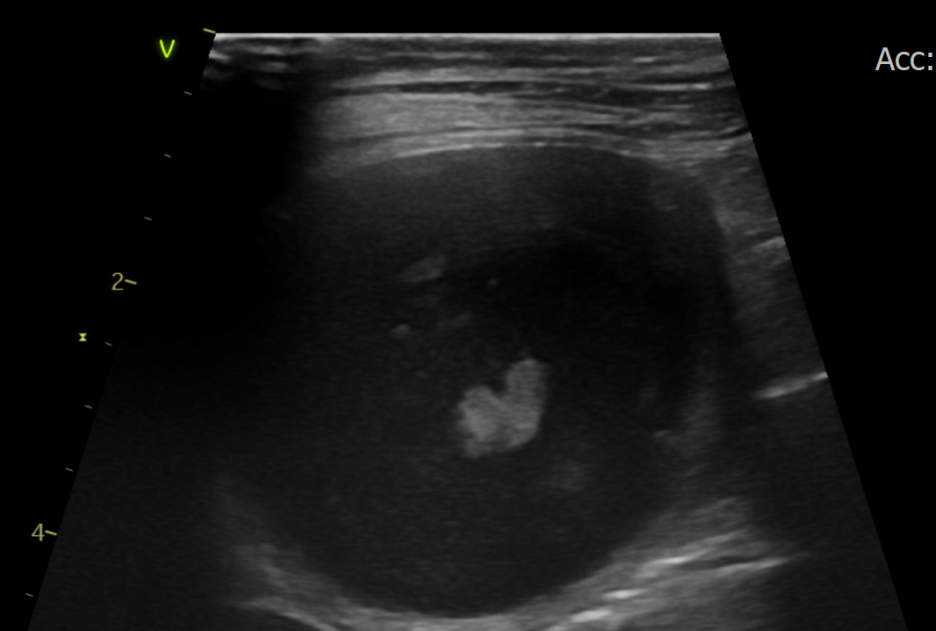

복부초음파 결과 / 출처: 24시온숲동물의료센터

복부초음파·방사선검사 결과

- 내원 당시 시행한 복부 초음파 및 방사선 검사에서 정상적으로는 4mm 정도 두께인 자궁이 약 4cm까지 심하게 확장되어 있는 모습이 확인되었습니다. 내부에는 고름으로 추정되는 내용물이 가득 차 있었으며, 이는 전형적인 자궁축농증의 소견에 해당합니다.